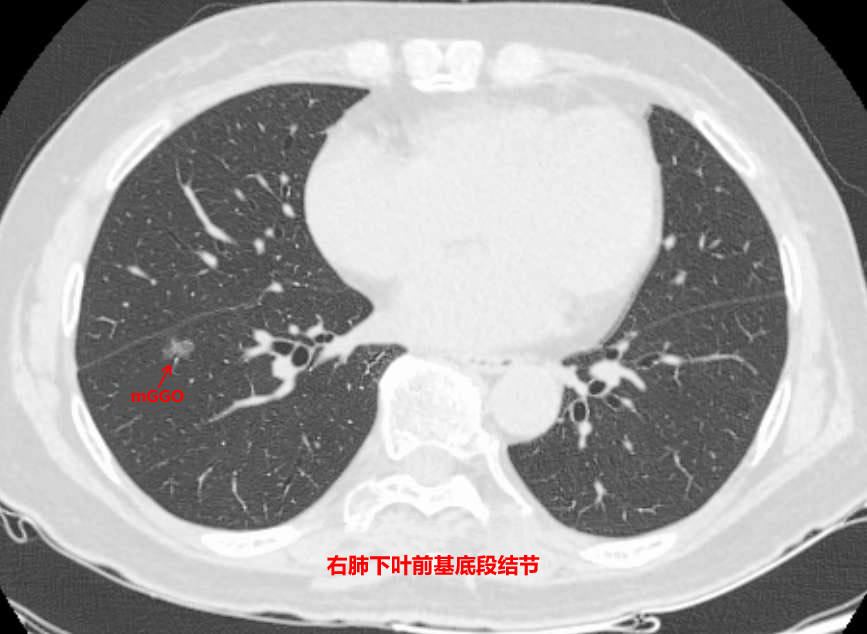

9月初,74岁的韦阿姨因膝关节疼痛来到国壮就诊,在拍摄胸部CT时,发现右下肺结节(部分实性结节),大小约9×12mm,边缘呈浅分叶改变,相应斜裂受牵拉。

根据密度差异,肺结节可分为三类:磨玻璃样结节、实性结节和部分实性结节。磨玻璃肺结节生长较为缓慢,实性结节生长速度较快,而部分实性结节肺癌可能性最大。因此,当肺结节在随访期间增大或实性成分增多,则建议积极手术治疗。